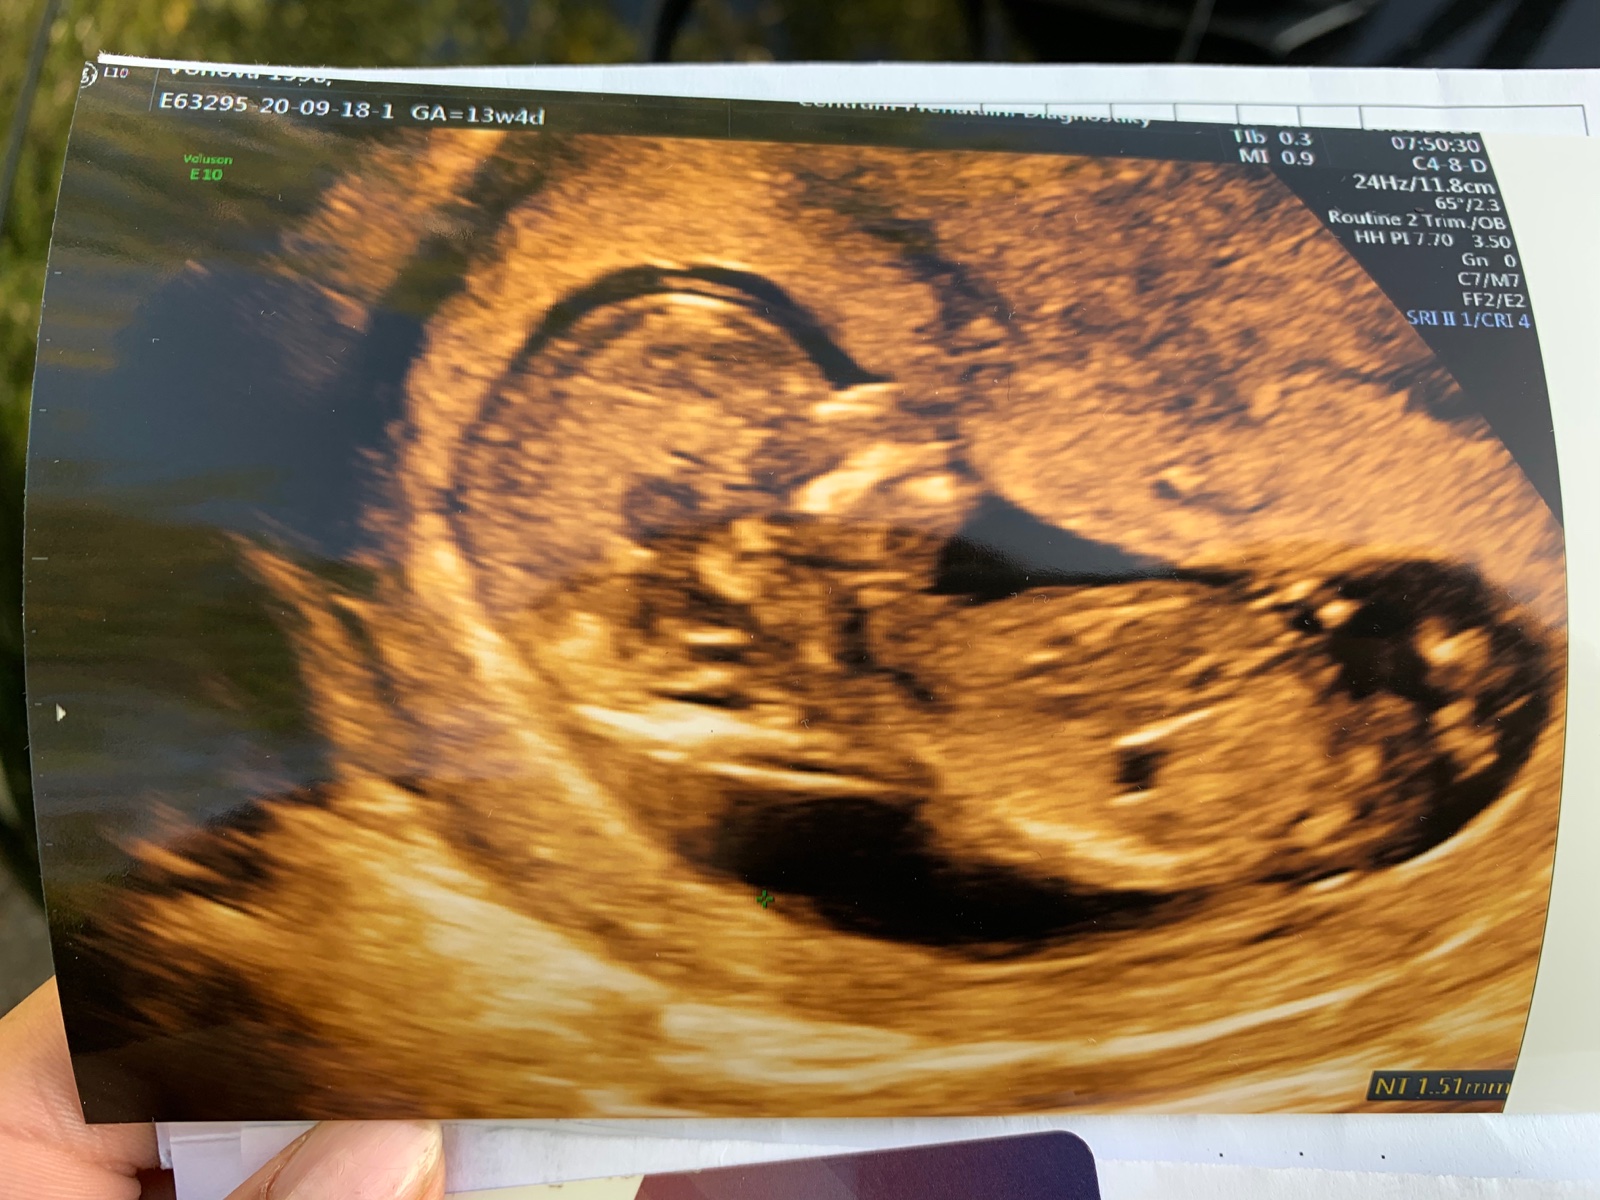

Pohlavní hrbolek. Je vidět?

@lenka253 Že by tohle a holčička?